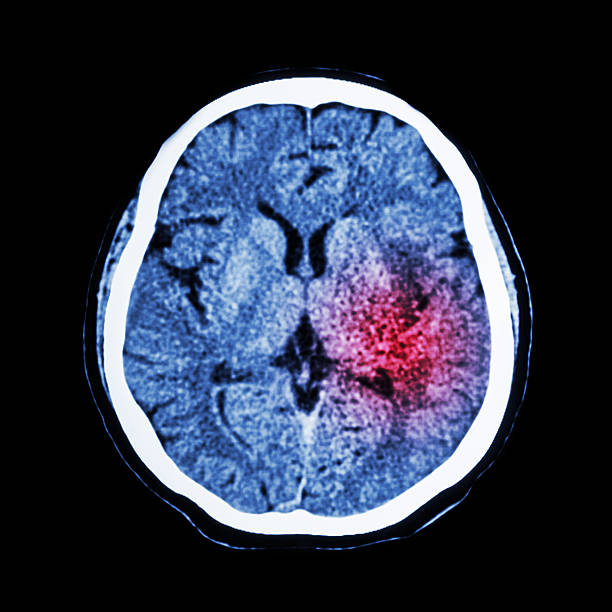

뇌출혈은 두 개 내에 출혈이 있어 생기는 모든 변화를 말하는 것으로 가장 큰 원인으로는 고혈압 증상을 지목하곤 합니다. 고혈압은 산소와 영양소가 뇌로 들어가는 통로인 혈관에서 변화를 일으키기 때문인데 뇌동맥류가 손상된 경우에도 발생할 수 있으며 잦은 흡연이나 음주 등 여러 원인으로 합병증으로 인해 발생할 수 있습니다. 특히, 뇌출혈 증상 발생시 가능한 빨리 병원으로 가야하고 약 2시간 안에 응급처치를 받아야 하는데 이는 응급처치를 받지 않으면 바로 뇌 손상으로 사망에 이를 수 있기 때문에 이번 시간에는 뇌출혈 전조증상에 대해 정리해 보겠습니다.